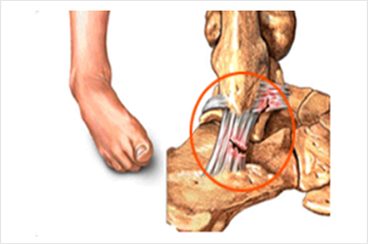

족저근막 유리술이란?

족저근막이 신경을 압박하는 주변 조직을 절개하고, 족저근막이 받는 부담을 낮춰 통증을 완화하는 수술입니다.

최소 절개로 흉터가 작고, 빠른 일상생활 복귀가 가능합니다.

발이 받는 부담이 줄어 들어 통증이 완화됩니다.

족저근막염

족저근막염이 생기는 원인

• 조깅, 등산, 마라톤, 축구 및 농구와 같은 구기종목을 과도하게 할 경우

• 딱딱한 바닥에서 장시간 서 있거나 반복적으로 점프할 때

• 체중이 급격히 증가할 경우

• 하이힐을 장시간 착용하고 보행할 경우